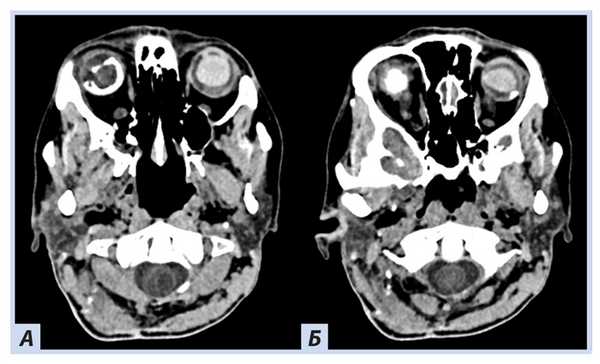

Рис. 2. Пациентка П., 30 лет, с диагнозом «Болезнь Гиппеля−Линдау»: компьютерная томография головного мозга

Примечание. Отмечаются гиперденсные зоны в области сетчатки и глазных яблок справа плотностью до +270…+330 HU.

При скрининговом ультразвуковом исследовании забрюшинного пространства были выявлены изменения обеих почек, которые были интерпретированы как множественные кисты при дообследовании на КТ забрюшинного пространства: множественные кистозные образования обеих почек; в верхнем полюсе левой почки — кистозно-солидное образование, изоденсное паренхиме почки в нативную фазу (40 HU), в артериальную активно накапливающее контраст (до 100 HU), контуры его четкие неровные (рис. 5, 6).

Рис. 5. Пациентка П., 30 лет, с диагнозом «Болезнь Гиппеля−Линдау»: компьютерная томография забрюшинного пространства

Примечание. А — нативная фаза: кисты обеих почек, солидный узел в верхнем полюсе левой почки; Б — артериальная фаза: кисты обеих почек более отчетливы на фоне контрастированной почечной ткани, солидный узел в верхнем полюсе левой почки с неоднородным накоплением контраста опухолью.

Рис. 6. Пациентка П., 30 лет, с диагнозом «Болезнь Гиппеля−Линдау»: компьютерная томография забрюшинного пространства

Примечание. А — нативная фаза: кистозно-солидное образование левой почки; Б — артериальная фаза: кистозно-солидное образование левой почки с неоднородным накоплением контраста опухолью.

При ультразвуковом исследовании поджелудочной железы эхографическая картина неотчетлива, по данным КТ паренхима поджелудочной железы диффузно изменена за счет множественных тонкостенных кист, вирсунгов проток не прослеживается (рис. 7).

Рис. 7. Пациентка П., 30 лет, с диагнозом «Болезнь Гиппеля−Линдау»: компьютерная томография поджелудочной железы

Примечание. А — нативная фаза: множественные тонкостенные кисты поджелудочной железы; Б — артериальная фаза: кисты визуализируются более отчетливо на фоне контрастированной окружающей ткани железы, но при этом участков патологического накопления поджелудочной железой нет.